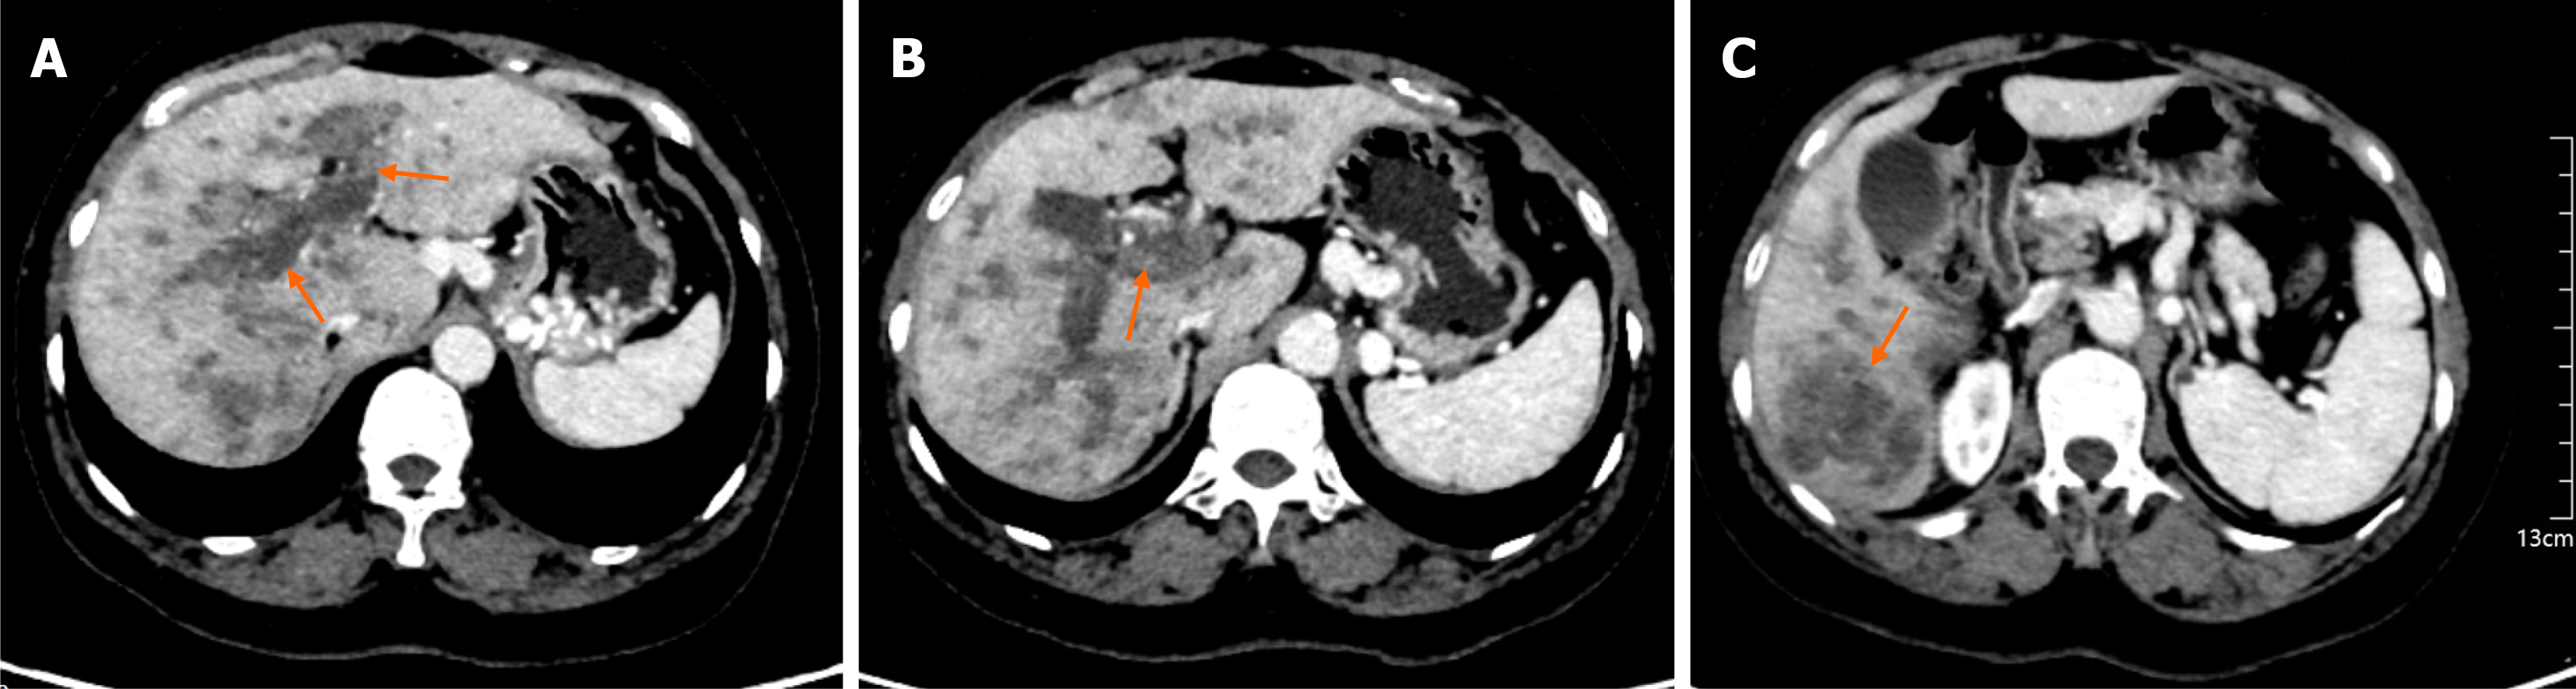

Figure 1 Contrast-enhanced abdominal computed tomography (portal venous phase).

A: Thrombus in the left and right branches of the portal vein; B: Thrombus within the main portal vein; C: A mass of approximately 5.1 cm × 5.0 cm in the right lobe of the liver.